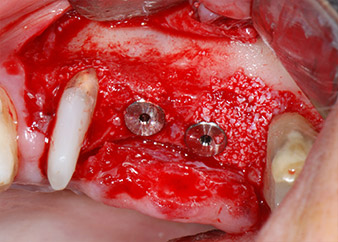

One month later, on the day of surgery, pain and inflammation at tooth 24 were minimal, but mobility of Miller class 2 was still present. After opening the flaps and cleaning the periapical and peri radicular infected tissue, the extent of the bone defect became obvious (Figs. 2 and 3).

At the buccal root, all vestibular and distal bone was missing. Attachment was essentially restricted to the palatal root, underlining the preliminary poor prognosis. Tooth 27 also showed a reduced horizontal attachment and a minimal apical rarefaction (cf. Fig. 1) without clinical symptoms.

However, we maintained our initial plan to retain both teeth as temporary bridge abutments during the six-months osseointegration period of the implants. At reentry, the situation would have to be reassessed. First, in an attempt to manage the endo-perio problem, the remaining root surface was carefully debrided with piezoelectric equipment (Piezomed, W&H, used with the spatula-shaped insert S1, originally designed for erosion of the lateral sinus wall) (Fig. 4).